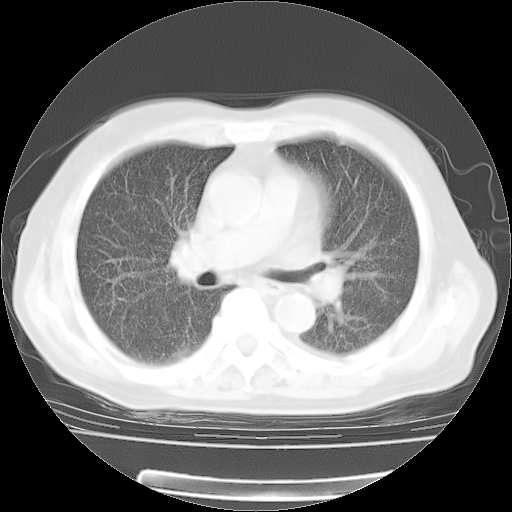

4月28日肺部CT——再次出现类似去年5月9日——透光度降低,“间质性”改变。

4月28日肺部CT——再次出现类似去年5月9日——磨玻璃样、间有“粟粒样”改变。

个人阅读4.14日肺部CT平扫:纵隔窗无异常,但肺窗示:双下肺内、后基底段有片絮状侵润影,部位以后基底段为著,以间质改变为主,呈急性肺泡炎征像,和首次住院影像学有相似之处。仅是个人读片,明日请相关专家再读片哈。其它建议同上。